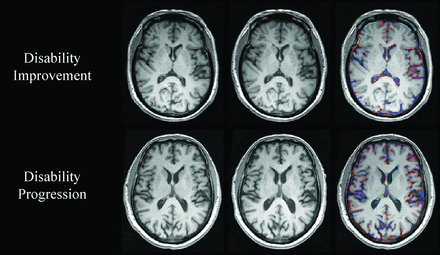

On-line Table 2 shows PLVVC and PBVC in disability progression, disability improvement, and stable groups. Figures 1 and 2 show representative changes of PLVVC and PBVC in disability progression and disability improvement in individual patients during follow-up, respectively. At baseline, there were no significant LVV and whole-brain volume differences among patients with MS in the disability progression, disability improvement, and stable groups.

Change in whole-brain volume in patients with MS with disability improvement and disability progression. In the upper and lower rows are shown patients with MS with disability improvement and disability progression, respectively. From left to right are baseline and follow-up 3D-T1WI, and a SIENA brain volume change edge map showing areas of atrophy (in blue-light blue) and growth (in red-yellow). Please note the higher annualized PBVC rate in disability progressed (−2.4%) compared with disability improved (−0.5%).

The annualized PBVC was −0.7% ± 0.7% in the disability improvement, −0.8% ± 0.7% in stable, and −1.1% ± 1.1% in disability progression groups (adjusted P = .001). The disability improvement group had significantly lower total (adjusted P = .01) and annualized (adjusted P = .02) PBVC compared with the disability progression group. The stable group had significantly lower total (adjusted P < .001) and annualized PBVC compared with the disability progression group (adjusted P = .01). The disability improvement group did not show a significant difference in total (adjusted P = 1.0) or annualized PBVC (adjusted P = 1.0) compared with the stable group. The estimated means and 95% confidence intervals for the analyses are shown in On-line Table 3.